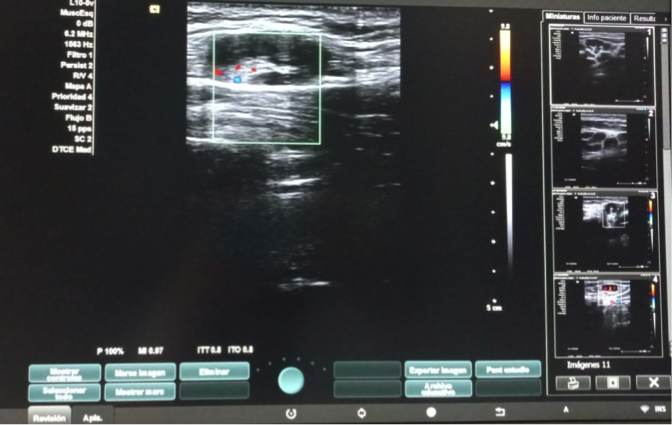

Hallazgos ecográficos

Dos adenopatías en territorio laterocervical derecho, con hilio central y doppler positivo, alguna con diámetro transversal superior al longitudinal, de probable origen reactivo y una adenopatía supraclavicular sin hilio central y con vascularización generalizada.

A las dos semanas de iniciar el tratamiento con ibuprofeno, se realiza el control ecográfico que evidencia ganglios cervicales bilaterales, inespecíficos de probable carácter reactivo y menores de 10 mm en el eje corto, por lo que finalmente se decide no exéresis de adenopatía.